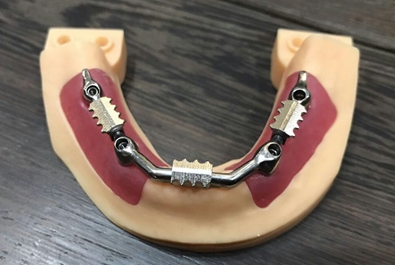

毛國斌種植病例——群討論分享